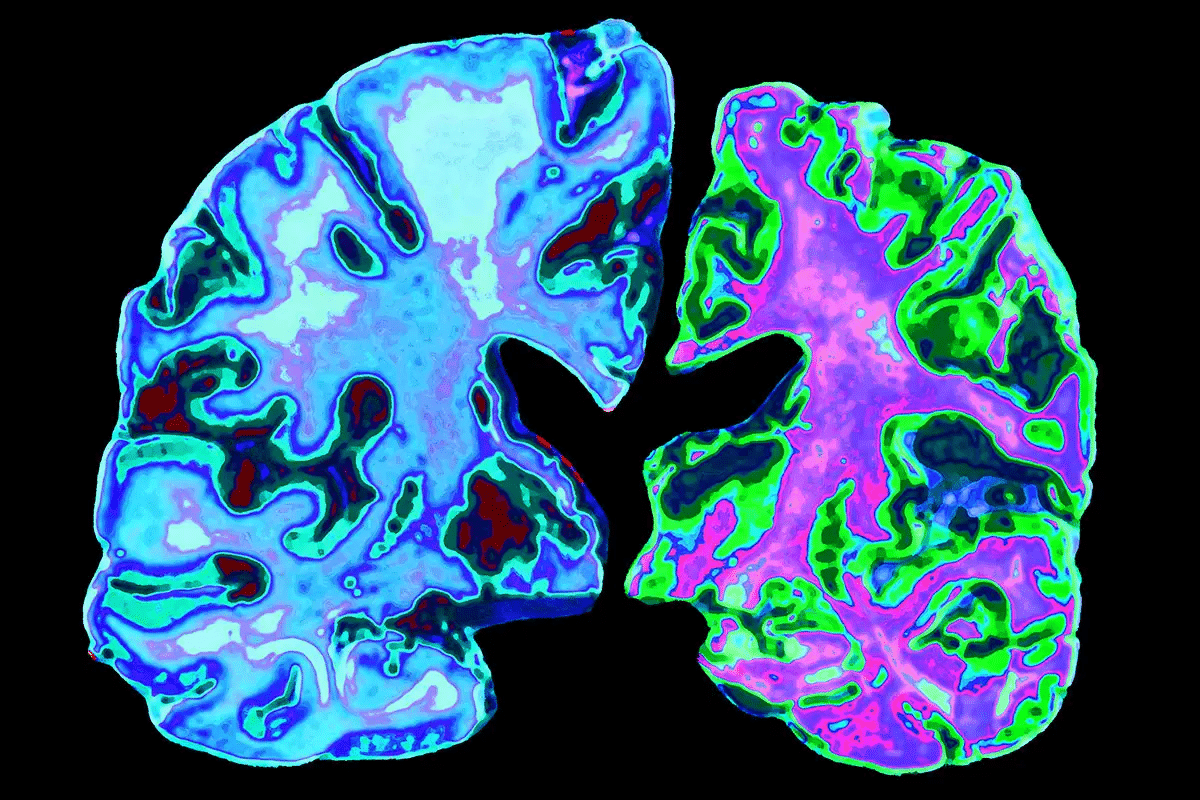

Anatomical Distribution in the Brain

Amyloid plaques and neurofibrillary tangles have a specific pattern in the brain. This pattern is key to understanding Alzheimer’s disease. They mainly affect the neocortex and hippocampus, leading to cognitive decline.

Affected Brain Regions

The neocortex is hit hard by amyloid plaques. It’s key for processing sensory info, controlling movement, and thought. The hippocampus, important for memory, is also damaged by neurofibrillary tangles.

Other areas like the entorhinal cortex and amygdala are also affected. This adds to the complex symptoms of Alzheimer’s disease.

Progression Patterns

The growth of amyloid plaques and neurofibrillary tangles follows a pattern. They first show up in the hippocampus and entorhinal cortex. These areas are vital for memory.

As the disease gets worse, plaques and tangles spread to other parts of the brain. This includes the neocortex, causing widespread damage to neurons.

Impact on Neocortex and Hippocampus

The neocortex and hippocampus are very sensitive to these changes. The buildup of plaques and tangles in these areas harms normal brain function. This leads to memory loss and cognitive decline.

Understanding how these areas are affected is vital. It helps in finding effective treatments for Alzheimer’s disease.